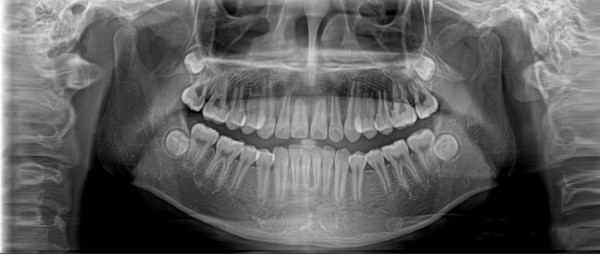

全景機基于體層攝影原理設(shè)計而成,全景攝影時,根據(jù)口腔頜面部的解剖特點,X線球管圍繞人體頭部選擇約120°,從一側(cè)顳下頜關(guān)節(jié)到另一側(cè)顳下頜關(guān)節(jié),最后一次性獲得全口牙齒的2D圖像,使頜骨及全口牙體層攝影在一幅圖片上呈現(xiàn)左右展開的平面圖。

全景機具有觀察全面、操作簡便、兒童及老弱患者容易接受的優(yōu)點。然而,全景機的缺點也非常明顯:

1.相較牙片機,全景成像中牙齒內(nèi)部的清晰度和細(xì)節(jié)明顯要略遜一籌;

2.由于是曲線體層成像,其圖像有比較嚴(yán)重的畸變失真,同樣也不可避免的具有影像重疊。

因此,全景機主要用于觀察所有牙齒的形態(tài)、位置及頜骨內(nèi)情況,為牙齒正畸矯正、牙齒修復(fù)提供圖像依據(jù),不太適合用于對牙齒結(jié)構(gòu)成像清晰度要求非常高的領(lǐng)域。